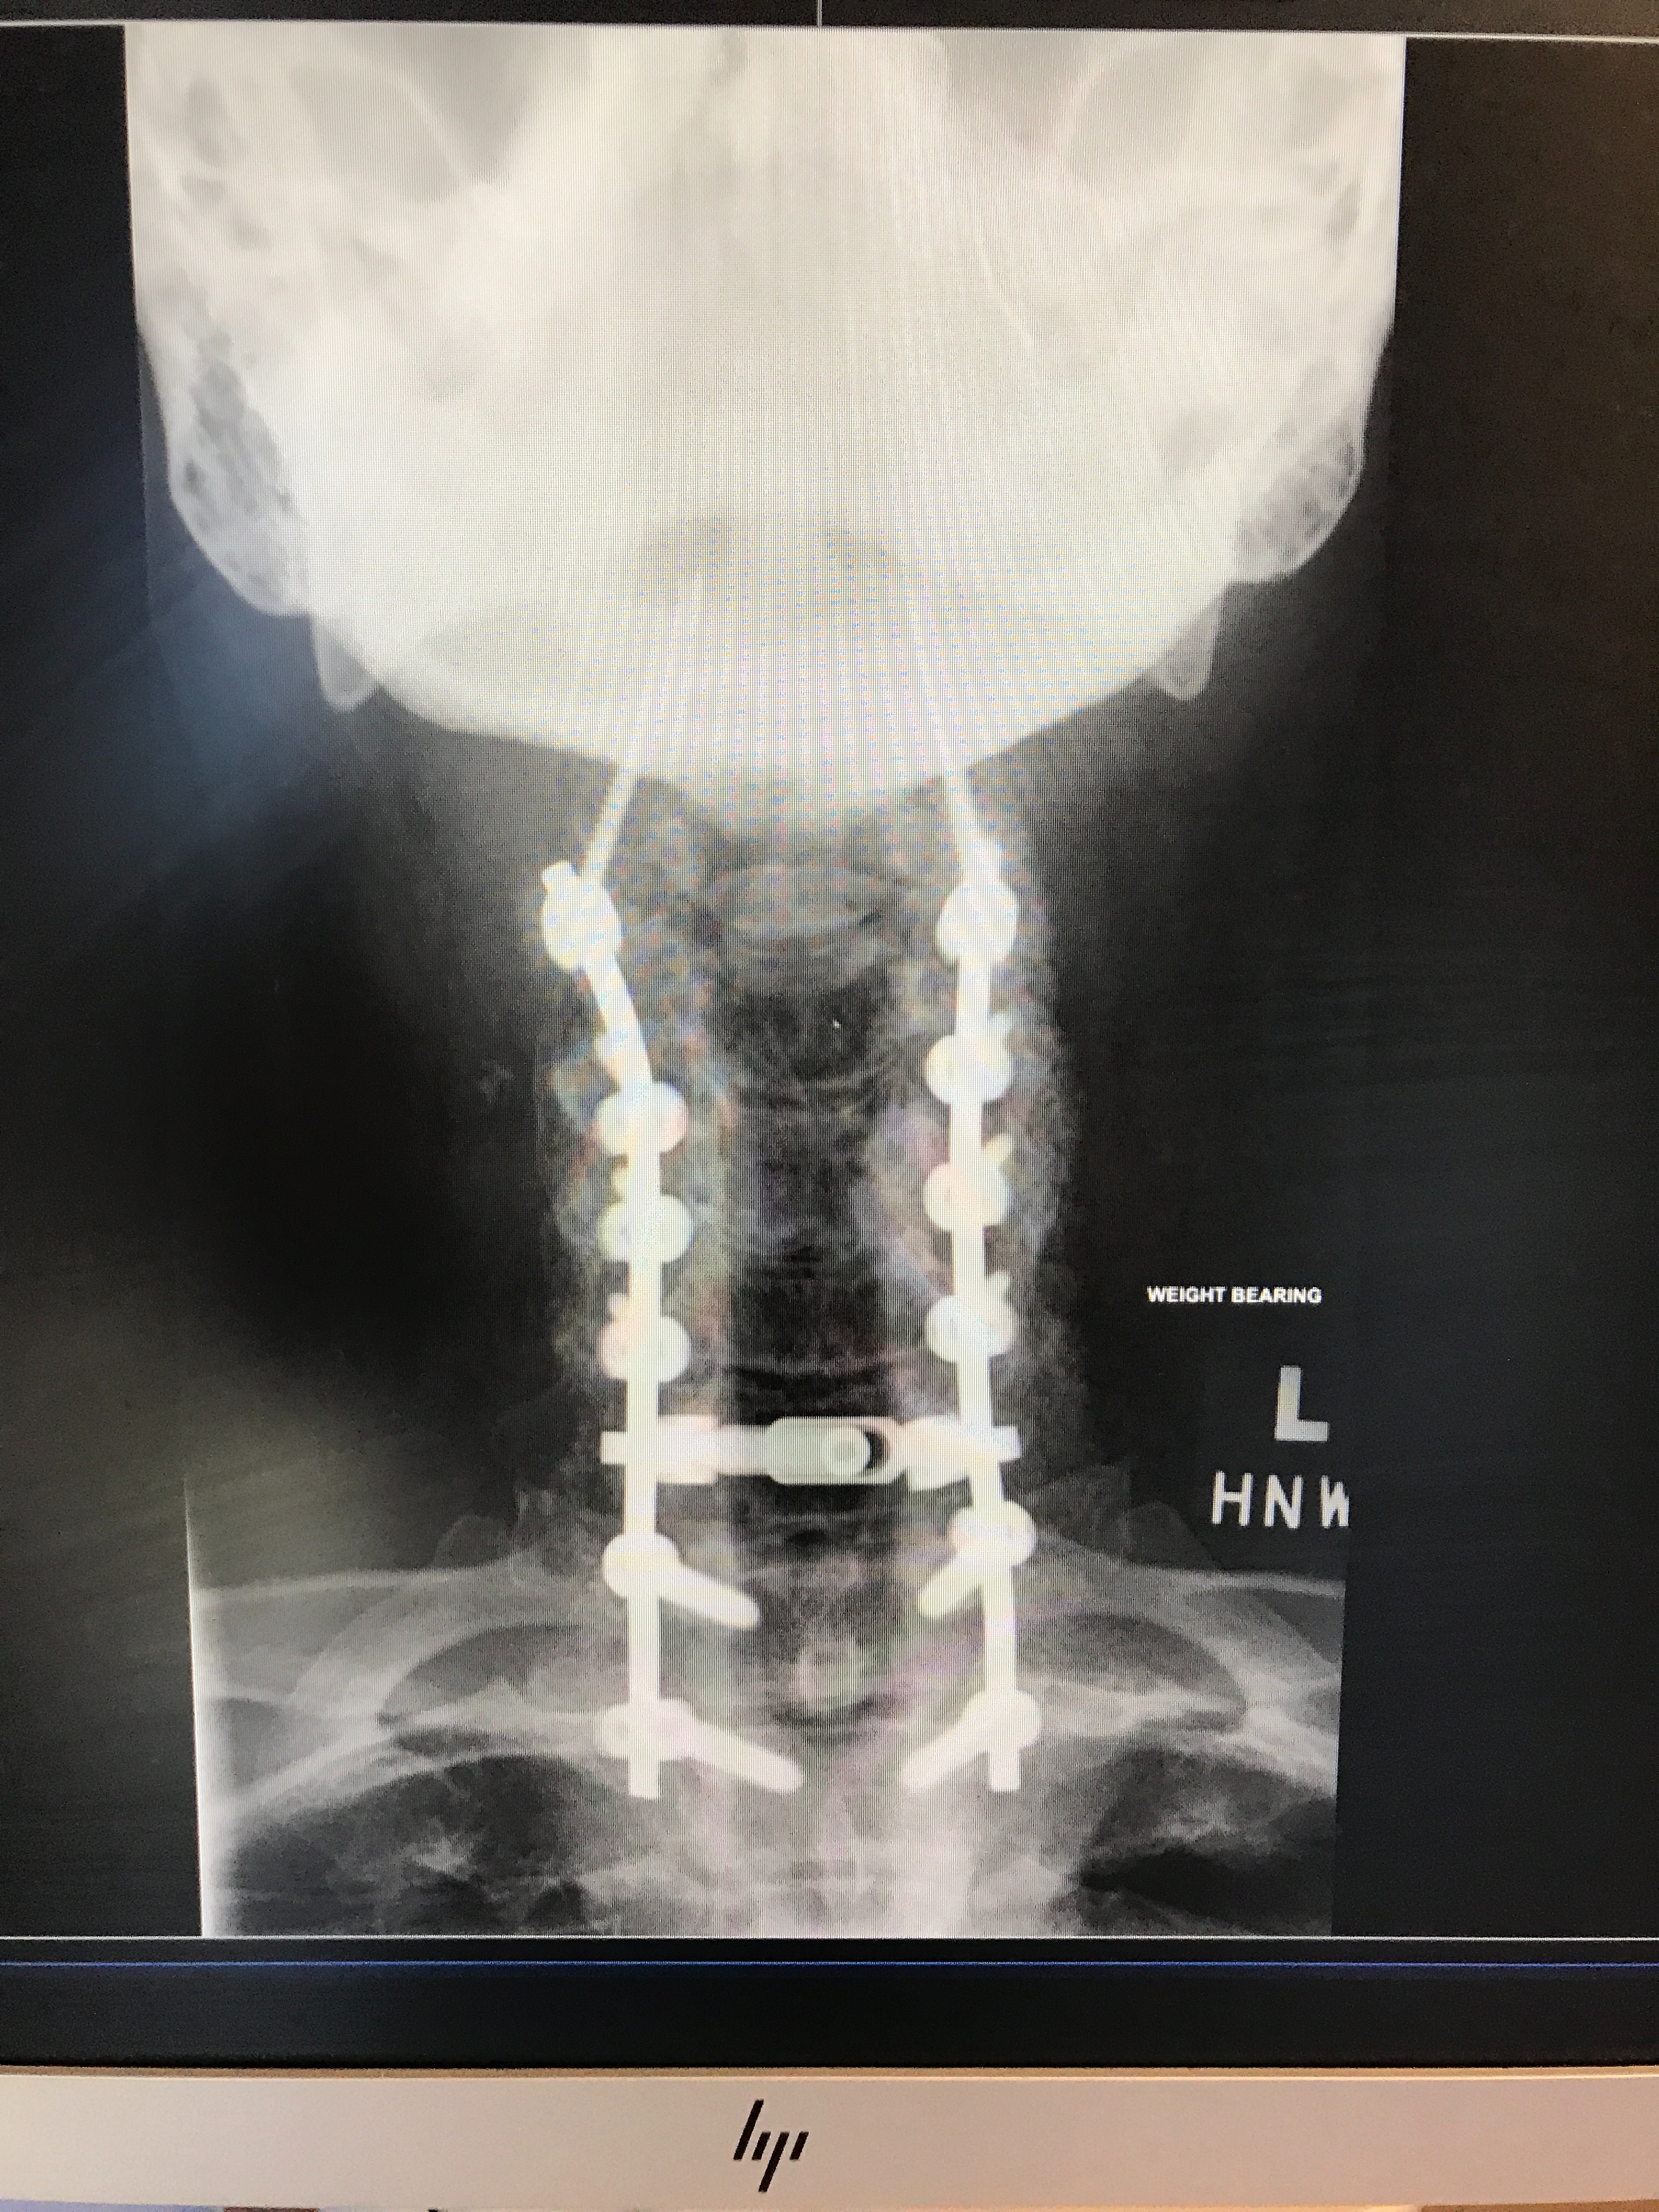

For most of my life, I have been fortunate with my health. However, my journey changed course in 2016 with a diagnosis of Degenerative Spine Disease, which led to multiple surgeries and a gradual decline in my health.